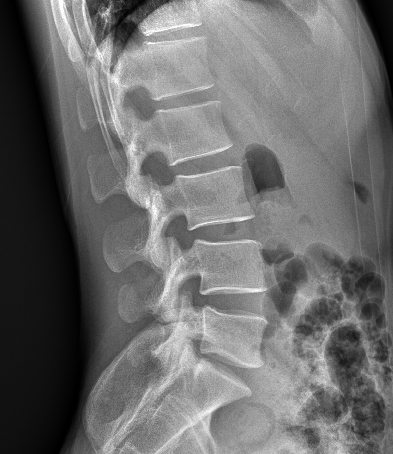

平板探测器

超高像素

高清点片